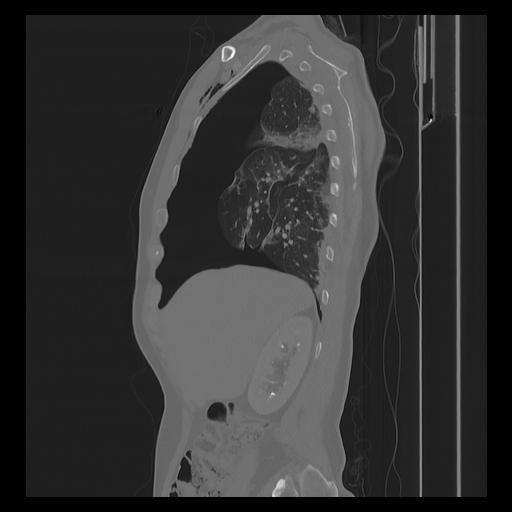

33 PULMON,CE,Sagittal,3.000,PULMON,Sagittal,